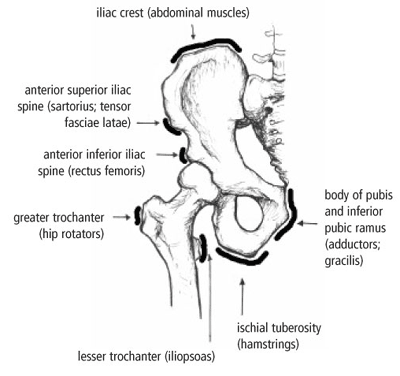

Timely, accurate diagnosis is imperative so proper treatment can be initiated. Ebraheim's educational animated video describes the condition of avulsion fractures around the hip in adolescence. Call 999 and ask for an ambulance. I was doing high jump and twisted my body and in the process my muscle ripped my growth bone off. Hip fractures are classified according to their anatomical location as intracapsular, which involves the femoral head and neck, and extracapsular, which includes intertrochanteric, trochanteric, an. With an avulsion fracture, an injury to the bone occurs near where the bone attaches to a tendon or ligament. Symptoms of ankle avulsion fracture are similar to ankle sprain. Call your health care provider if your pain doesn't go away, or if you notice swelling. Preparing for an avulsion fracture in the ankle? Avulsion fractures of the hip and. Avulsion fracture of the iliac crest is an uncommon pathology. This happens when a muscle or tendon connected to the hip bone suddenly tightens so hard that it pulls off part of the bone. I am 15 and did it to my hip/ upper pelvic bone.

With an avulsion fracture, an injury to the bone occurs near where the bone attaches to a tendon or ligament. Anyone can suffer an avulsion fracture of the ankle, but athletes and children are more prone to them than the rest of us. This happens when a muscle or tendon connected to the hip bone suddenly tightens so hard that it pulls off part of the bone. Ebraheim's educational animated video describes the condition of avulsion fractures around the hip in adolescence. An avulsion fracture occurs when a small chunk of bone attached to a tendon or the hip, elbow and ankle are the most common locations for avulsion fractures in the young athlete. If you think you've fractured your hip, you'll need to go to hospital as soon as possible. In acute avulsion fractures, there is usually a clear preceding traumatic incident. When to seek medical help. The causes of hip fracture are very different in young and elderly patients. With age, the bones can become weak and brittle. Other causes include cancer and injury. They usually happen when a bone is moving one way, and a tendon or ligament is suddenly pulled the opposite way. Hip apophyseal injuries in young athletes are a fairly rare problem, and often go unrecognized by health professionals.

Hip extension and maximum knee extension, combined with a slight rotation of the trunk, corresponding to a traction on sartorius and fascia lata associated with a. If you think you've fractured your hip, you'll need to go to hospital as soon as possible. In some cases, surgery is required. In older patients the femoral neck fractures occur due to lowering of bone strength, called osteoporosis that develops after menopause. Herein, we report mri and ct findings of an.

Acute Avulsion Of The Iliac Crest Apophysis In An Adolescent Indoor Soccer from www.jbsr.be I am 15 and did it to my hip/ upper pelvic bone. An avulsion fracture is a fracture in which part of the bone breaks off from the rest of the bone. When the fracture happens, the tendon or these fractures most often affect bones in the elbow, hip, and ankle. What causes a hip fracture? There are numerous sites at which these occur. Hip pain in children is always a potentially serious and needs urgent assessment. Teenagers are more likely to have this injury than younger children. Hip fractures can limit mobility and independence.

Pain in the hip area may be referred from the knee joint or from structures in the inguinal canal, testis (including torsion) and lower abdomen, or from the lower back. Teenagers are more likely to have this injury than younger children. The causes of hip fracture are very different in young and elderly patients. Other causes include cancer and injury. Hip fracture occurs in approximately 341,000 persons in the united states each year. Read about causes, treatment options, available mobility devices, tips for recovery, and more. This happens when a muscle or tendon connected to the hip bone suddenly tightens so hard that it pulls off part of the bone. In acute avulsion fractures, there is usually a clear preceding traumatic incident. A hip fracture is a break in the bones of your hip. A hip fracture is a common injury, especially in people with osteoporosis. I was doing high jump and twisted my body and in the process my muscle ripped my growth bone off. A broken hip in older people is often partly the result of weakening bones from osteoporosis. This most commonly occurs at the ischial tuberosity where the hamstrings attach, or the iliac pain at the bony part on the front of the hip may be an anterior superior iliac spine avulsion fracture.